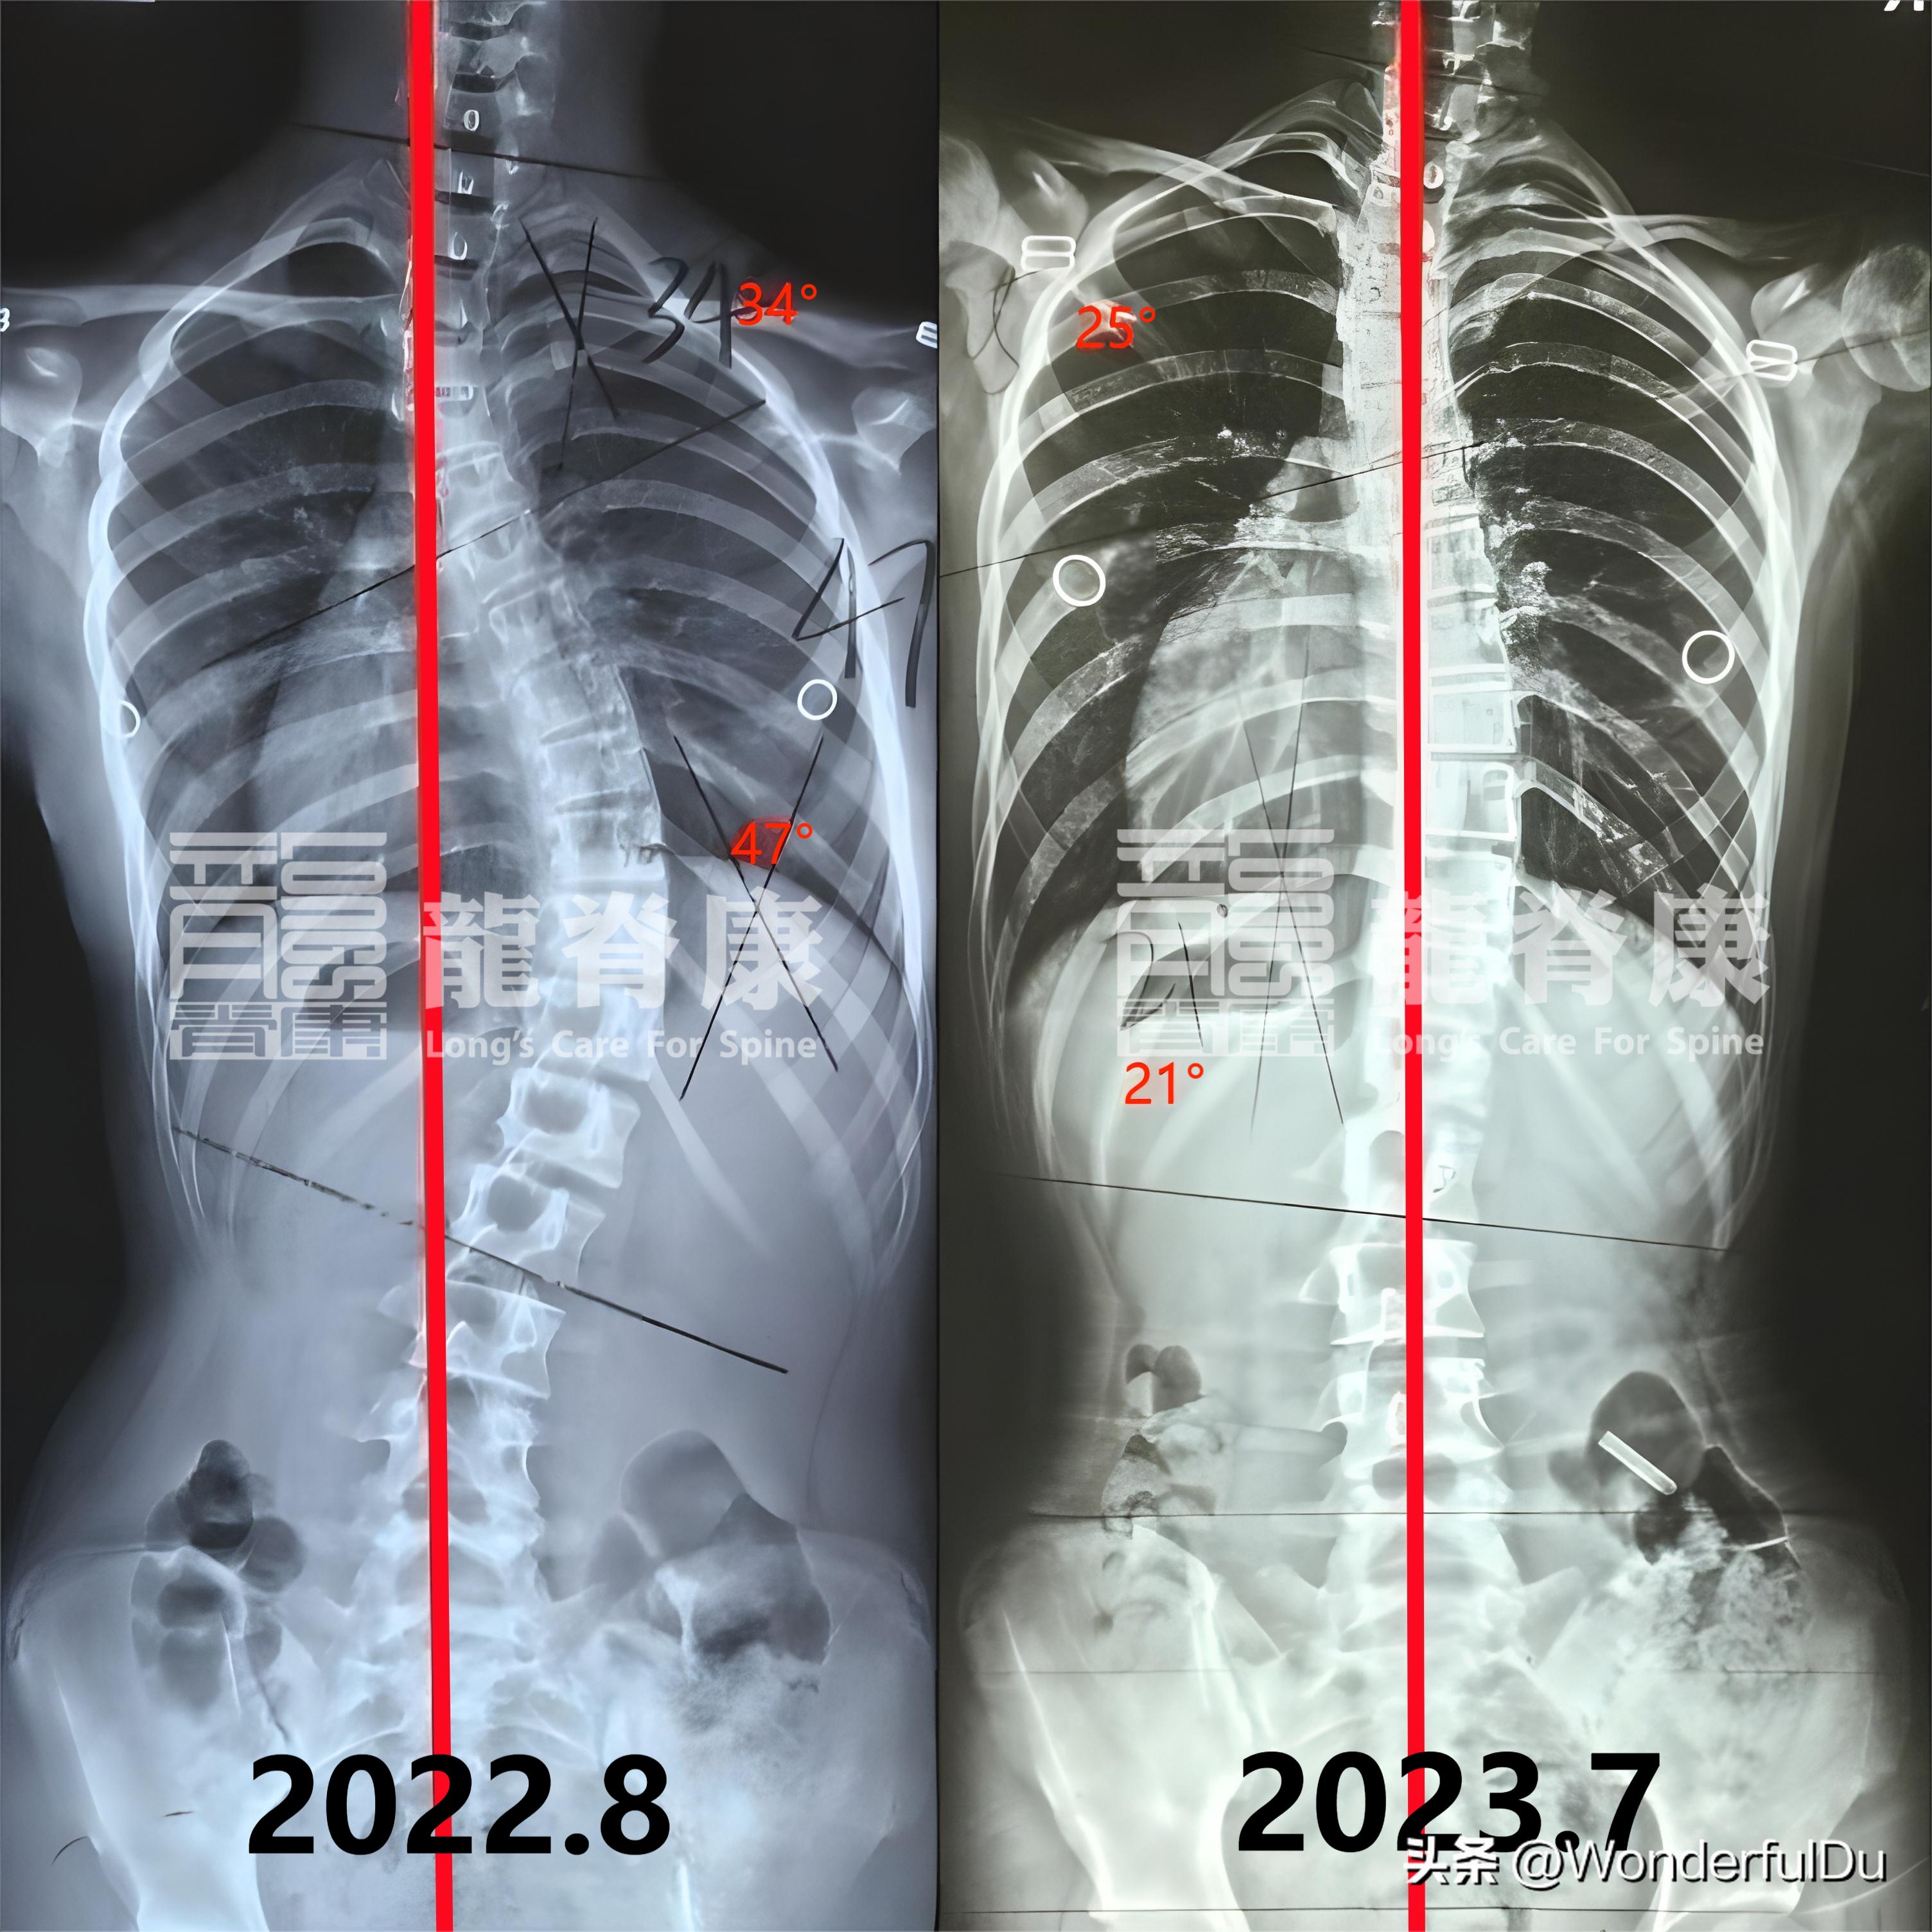

女孩小雨今年15岁,1年前练习瑜伽时被老师发现背部不对称,右背明显凸起了一块,告知家长该情况后,第二天家长连忙带着孩子去本地医院拍片检查,发现了 S型脊柱侧弯 ,分别是 34°和47° ,身体整体向右侧偏歪。

就这样坚持了差不多一年的时间,回门诊复查时,小雨的 上胸弯从34°减至25° , 下胸弯从47°减至21° , 剃刀背从18°减至11° ,体表也比之前改善了不少,整体在往好的方向发展。

侧弯度数治疗前后对比

在这个案例中,小雨是14岁被发现侧弯的,Risser征4级, 并不算 是最佳的矫正年龄,但好在孩子身体柔韧性好,所以在支具的外力下,脊柱能很好地回推到中线,所以支具下拍片, 侧弯度数分别减至21°和9° 。